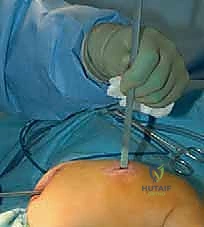

الخطوة الثالثة: بضع العظم المتعدد عبر الجلد (Multiple Percutaneous Osteotomies)

بدلاً من فتح الساق بالكامل، يقوم الدكتور هطيف بعمل ثقوب صغيرة جداً (مليمترات) في الجلد. باستخدام أدوات دقيقة جداً (مثل الإزميل الدقيق أو المثقاب المتخصص)، يتم قطع العظم في أماكن التقوس من الداخل دون إتلاف الأنسجة الرخوة أو العضلات المحيطة. هذا يحافظ على التروية الدموية للعظم (Periosteum)، مما يسرع من التئام العظم بشكل مذهل.

الخطوة الخامسة: الإغلاق والتجبير

نظراً لأن التدخل كان عبر ثقوب صغيرة، يتم إغلاقها بغرزة واحدة أو حتى بشريط لاصق طبي. يتم وضع جبيرة خفيفة أو دعامة لحماية الساق خلال الأسابيع الأولى من الالتئام. الألم يكون في حده الأدنى مقارنة بالطرق القديمة.